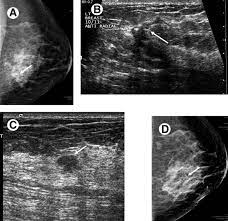

This breast cancer ultrasound image shows changes related to breast cancer that are not seen as microcalcifications or a mass or lump.

The age of the patient, large size of tumor and typical ultrasound features are highly suggestive of this being a phyllodes tumor of the left breast. During a breast exam, your doctor looks for visual changes and uses their fingers to feel. A mammogram image has a black background and shows the breast in variations of gray and white. Below are images of dcis on breast ultrasound. There is a slight increase in the density in the right breast compared with the left. You might get an mri. Breast infections can cause redness and swelling. Palpation of benign breast masses. Finding breast lumps and seeing change in the size and shape. This breast cancer ultrasound image shows changes related to breast cancer that are not seen as microcalcifications or a mass or lump. Any area that does not look like normal tissue is a possible cause for concern. Epidemiology these account for ~1% of breast cancers. If you have calcifications, they'll show up as white spots.

As the machine is moved over an area of the breast, the device sends sound waves into the tissue, and it shows an image based on how quickly those waves bounce back to it. Ultrasound does not use or. The lump may shows a combination of clustered tiny cysts and thickened parenchyma (arrows in c) Ultrasound may be particularly useful in detecting abnormalities in patients with dense breasts. Presenting radiologic appearance of breast dcis microcalcifications at breast cancer screening we can see from the chart above that overall, the most commonly occuring mammographic indication of dcis are the crushed stone microcalcifications.